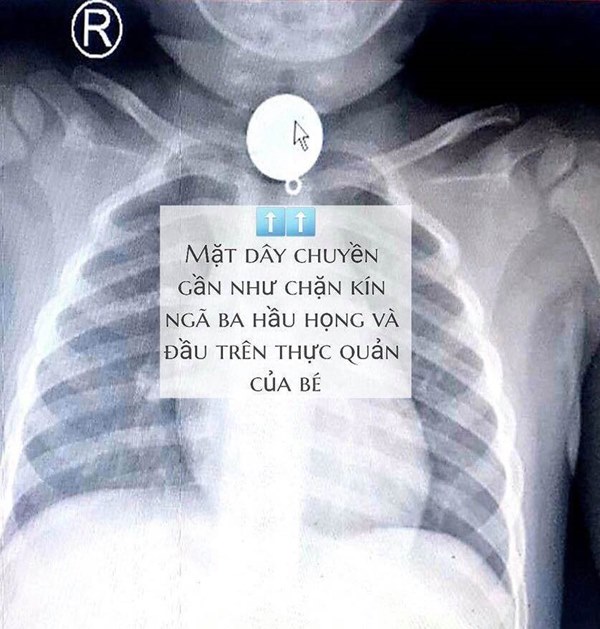

Tại bệnh viện, sau khi hội chẩn xác định dị vật mắc trong cổ bé rất to, hình tròn nằm chiếm hết lòng đầu trên thực quản, gần ngay ngã ba thông với đường thở, các bác sĩ nhận định khả năng dị vật gây trầy, rách thực quản, hay hóc ngược vào đường thở rất cao nếu xử trí không khéo.

Hình ảnh chụp X-Quang của bé trai.